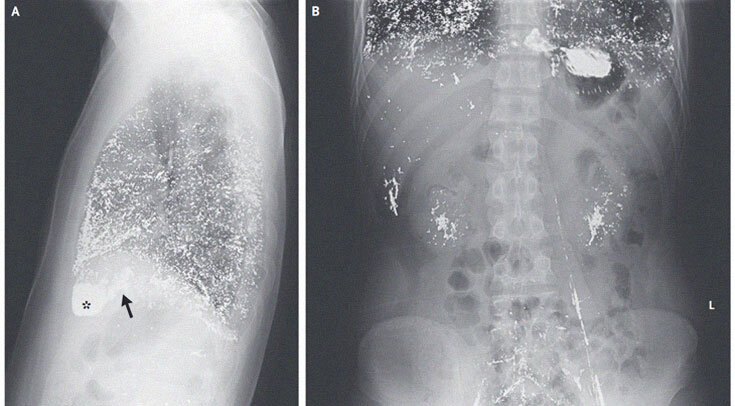

Рентгенограммы грудной клетки пациента в боковой проекции (A) и брюшной полости — в прямой (B). Стрелкой обозначено правое предсердие, астериском — правый желудочек Yunying Feng, Fengdan Wang / The New England Journal of Medicine, 2022

На рентгенограмме грудной клетки визуализировались диффузные затемнения, соответствующие отложениям ртути в легких, правом предсердии и правом желудочке. Снимок брюшной полости показал аналогичные депозиты в печени, почках, подвздошных и левой гонадной (яичковой) венах. На основании обследования мужчине поставили диагноз отравления ртутью.